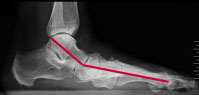

Mithilfe einer Röntgenuntersuchung des Fußes unter Belastung bestimmt der Orthopäde den Winkel zwischen Sprungbein (Talus) und erstem Mittelfußknochen (metatarsotalaren Index). Das Ergebnis ermöglicht ihm, das Ausmaß der Fehlstellung abzuschätzen.